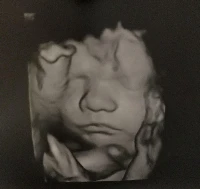

Az elmúlt héten töltöttem be a 30 hetet, így aktuálissá vált ismét egy nagyobb ultrahang. Nagyon izgultam előtte, hiszen az első babánkkal ez volt az utolsó vizsgálat, amin jártunk és ott még minden rendben volt.

A várandósságom úgy érzem legszebb hetén vagyunk túl! Jártam a védőnőmnél, ahol minden a legnagyobb rendben zajlott. Most már nem dolgozom, így bőven jut idő a pihenésre is. De ami a hetünk fénypontja volt, az a babamozi!